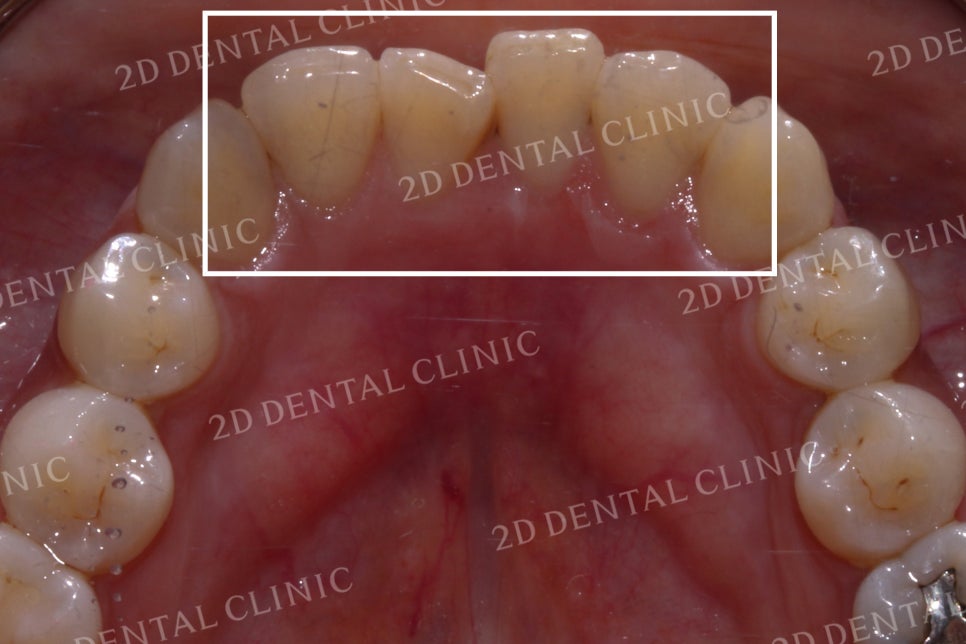

상악의 설측면 사진입니다.

위에서 말했던 것처럼

측절치가 설측면으로

과도하게 들어와 있는 모습입니다.